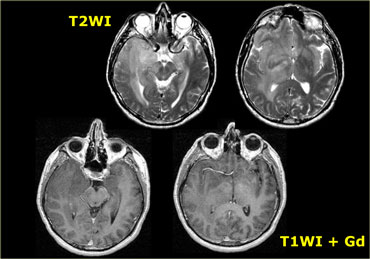

Schwannoma in CPA-region with typical features of an extraaxial tumor (T2WI) Schwannoma in CPA-region with typical features of an extraaxial tumor (T2WI)

The T2W-images show a schwannoma located in the cerebellopontine angle (CPA).

This case nicely demonstrates the typical signs of an extra-axial tumor.

There is a CSF cleft (yellow arrow).

The subarachnoid vessels that run on the surface of the brain are displaced by the lesion (blue arrow).

There is gray matter between the lesion and the white matter (curved red arrow).

The subarachnoid space is widened because growth of an extra-axial lesion tends to push away the brain.

All these signs indicate that this is a typical extra-axial tumor.

In the region of the CPA 90% of the extra-axial tumors are schwannomas.